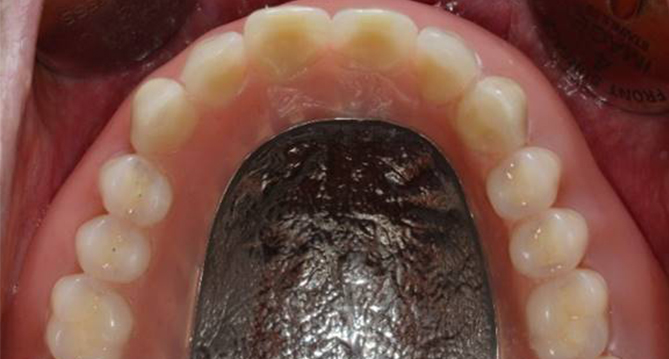

교합과 심미성을 모두 만족시키는

완벽을 추구하는 교정치료를 진행합니다.

풍부한 경험을 보유한 의료진이 직접 상담부터 유지, 치료까지 책임지고

개개인의 구강상태에 따른 적합한 최선의 치료계획을 수립하고 치료합니다.

개인의 얼굴형태나 아래위턱뼈의 형태, 성장발달 단계 등 여러가지를 고려해

치료계획을 세우는 교정은 정밀진단을 통한 올바른 치료가 중요합니다.